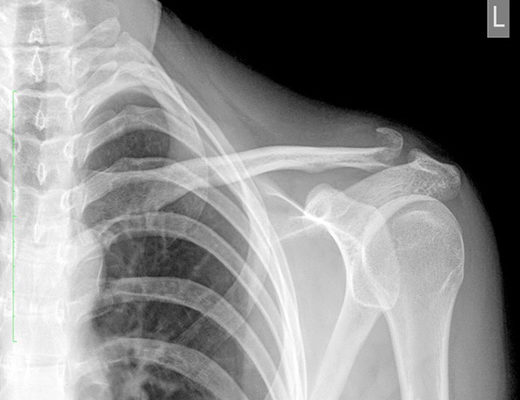

Перелом акромиального конца ключицы

Однако внешний осмотр не дает информации о точном характере травмы, поэтому следует сделать рентген. В сложных случаях перелома ключицы со смещением может быть проведена компьютерная томография или магнитно-резонансная томография. Определение степени и характера смещения перелома, наличия или отсутствия разрыва связок и вывиха определяет варианты лечения.